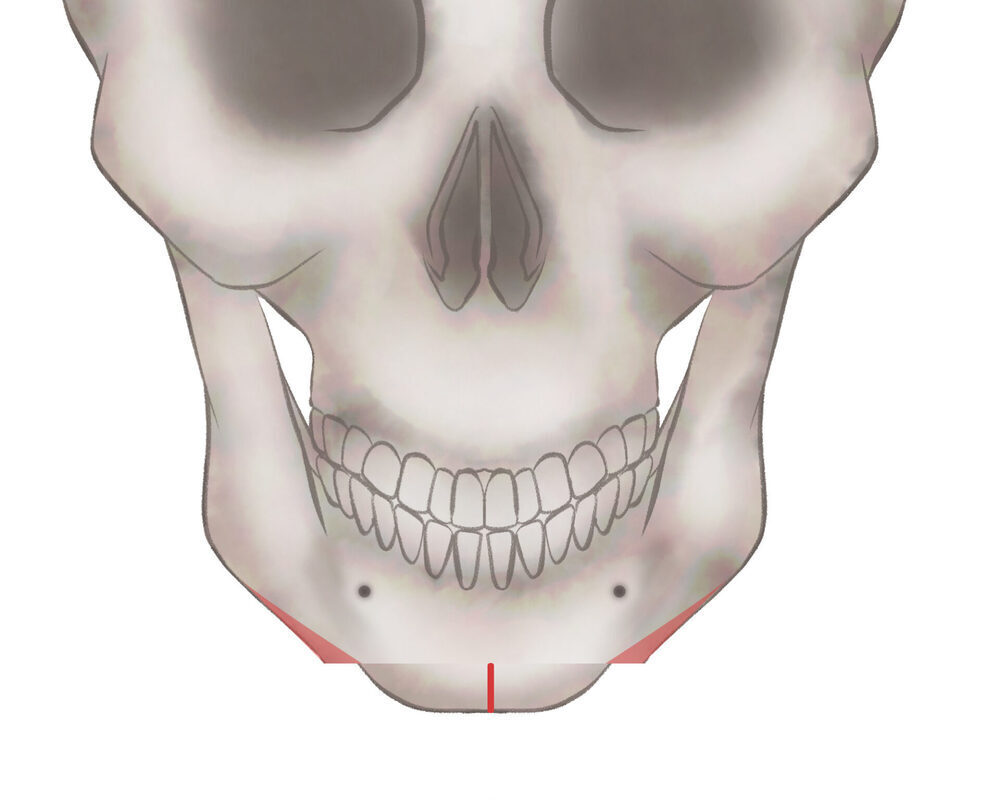

オトガイ骨切り(中抜き)

3.骨を移動させ段差を削ります

4.プレートで固定します